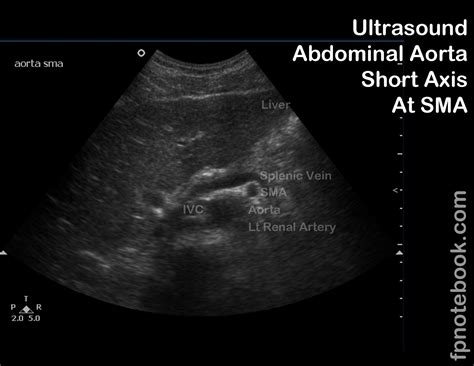

• Abdominal Aorta: Checking for aneurysms or other abnormalities in the abdominal aorta.

• Abdominal Aortic Aneurysm: The presence and size of an aneurysm in the abdominal aorta can be assessed.